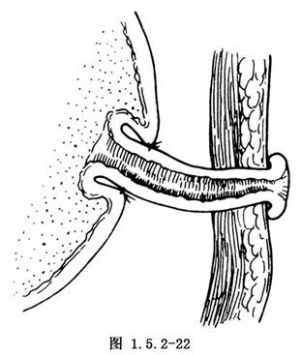

将胃前壁的管状组织经切口上端或另做切口拖至腹壁,切开及修整管状胃壁组织的远端并与皮肤切口缝合固定(图1.5.2-22)。